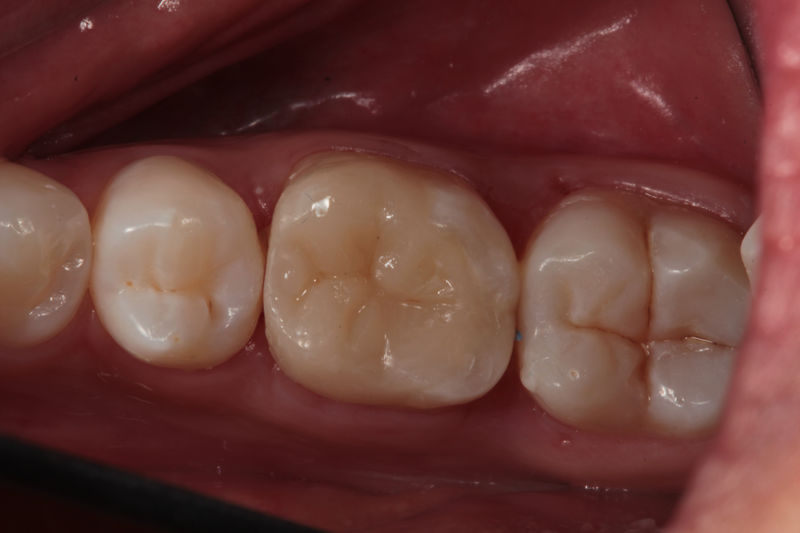

Disciplina fundamental de la Odontología enfocada en el diagnóstico, prevención y tratamiento restaurador de las piezas dentales que han sufrido daños. Su objetivo principal es devolver al diente su equilibrio biológico, funcional y estético cuando su integridad ha sido alterada. Resinas directas, incrustaciones, coronas.

Restauraciones fabricadas en el laboratorio con materiales estéticos, los cuales cubren de manera parcial dientes posteriores. Se utilizan primariamente para restaurar dientes con caries, fracturas y/o defectos amplios. Para poder enviar el caso al laboratorio se toman impresiones utilizando materiales de impresión o técnicas modernas digitales.

Restauraciones fabricadas en el laboratorio con materiales estéticos, los cuales cubren de manera total dientes anteriores y posteriores. Se utilizan primariamente para restaurar dientes con caries, fracturas y/o defectos amplios, así como soportes de puentes. Para poder enviar el caso al laboratorio se toman impresiones utilizando materiales de impresión o técnicas modernas digitales.